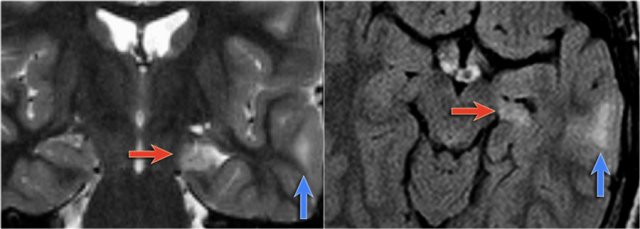

The coronal T2WI and FLAIR images show right-sided mesial temporal sclerosis.

Notice the volume loss, which indicates atrophy and causes secondary enlargement of the temporal horn of the lateral ventricle.

The high signal in the hippocamous reflects gliosis.

Coronal MR-images of a patient with Sturge-Weber show leptomeningeal enhancement in the right posterior hemispere.

CT in a patient with Sturge-Weber shows huge cortical and subcortical tram-track calcifications involving the left posterior hemispere.

4-year-old boy with Sturge-Weber syndrome.

Notice atrophy of the left posterior cerebral hemisphere with leptomeningeal enhancement and thickening.